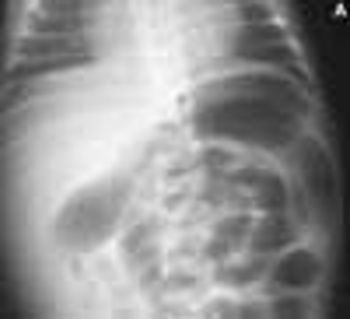

The wife of an 82-year-old man with Alzheimer's disease was concerned about her husband's poor posture. According to the woman, the patient had never sustained a back injury and had always maintained a sedentary lifestyle. He never smoked cigarettes and did not use alcohol. His history included multiple transient ischemic attacks (TIAs).